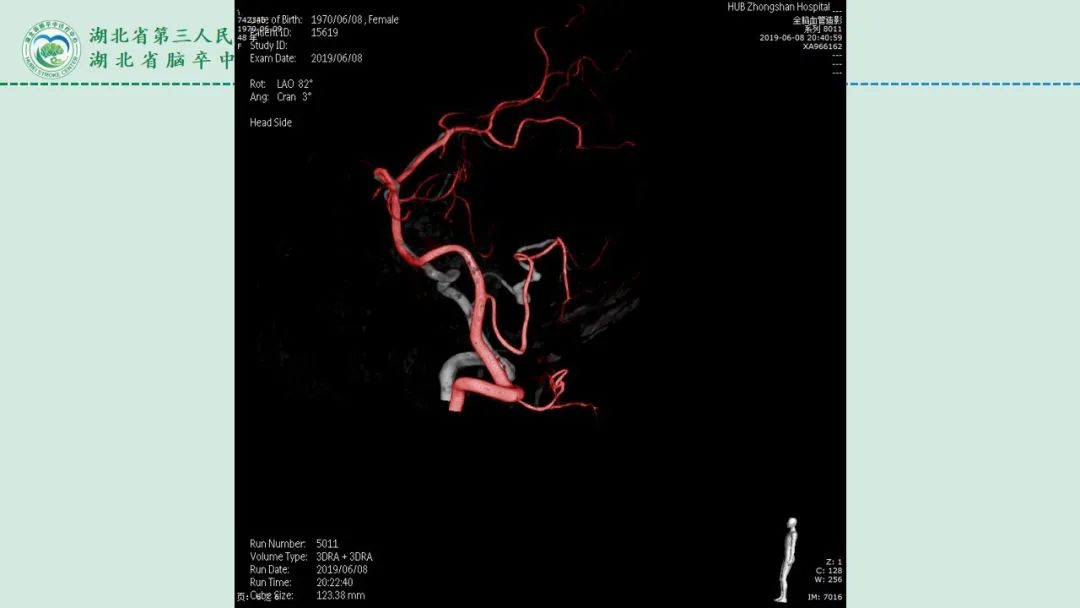

李俊教授团队:右侧PICA延髓扁桃体段多发动脉瘤

今日与大家分享的是《正海-妙术视界》第二百三十二期,由湖北省第三人民医院李俊教授团队带来的右侧PICA延髓扁桃体段多发动脉瘤,欢迎观看、分享。